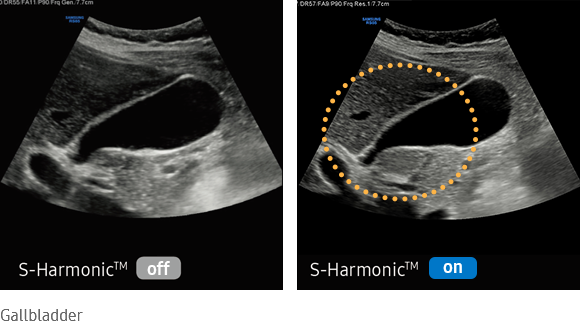

Uniform imaging performance of overall image area from near-to-far

This new harmonic technology improves image clarity, near to far. Reducing signal noise, S-Harmonic provides more uniform ultrasound images. Combined with the S-Vue transducers, S-Harmonic takes RS80 EVO image quality one step further.

imaging solutions  : S-Harmonic™